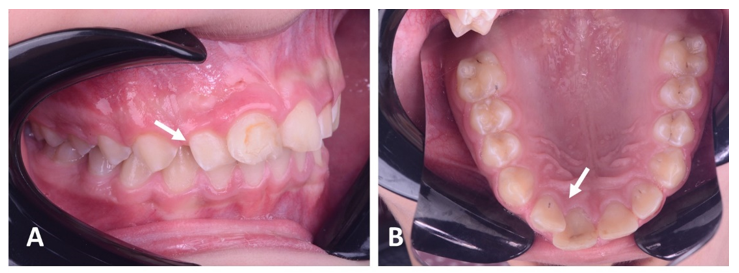

The patient did not report any painful symptoms during the 3-month rest treatment or at other follow-up visits. The case was clinically asymptomatic as all signs and symptoms had disappeared completely, and the gingiva appeared normal on follow‐up recall (Figure 3). Periapical radiographs show signs of healing of the periapical lesion, increasing radiopacity, and decreasing root divergence through follow‐up recall at 6, 12, and 18 months (Figure 4).

Figure 4 Periapical radiographs show increasing radiopacity and a decrease in root divergence through follow-ups at 6 (A), 12 (B), and 18 (C) months.

After 24 months, follow-up radiographs showed up-righting of tilted roots and a decrease in radiolucency of the lesion, reflecting healing with new bone formation. The severe displacement was corrected, and the patient no longer required orthodontic treatment (Figure 5).